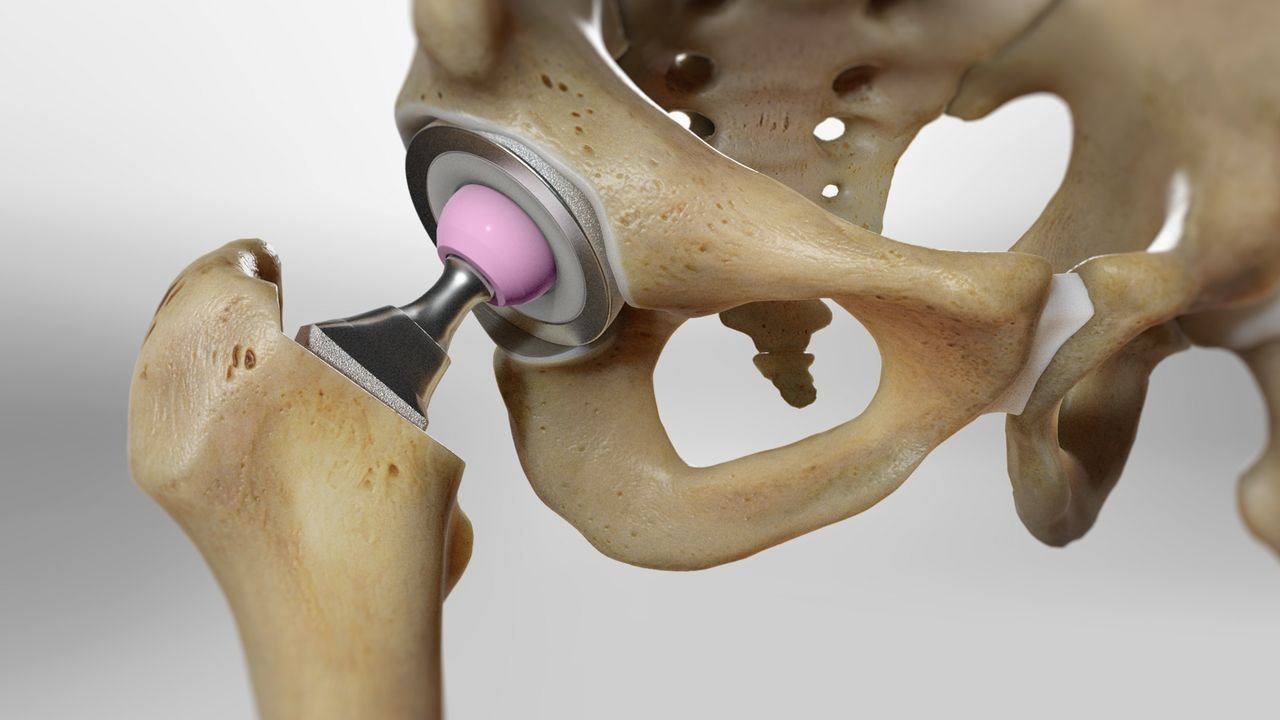

Hip Replacement Procedure at Kesarkar Hospital

At Kesarkar Hospital, we perform total hip replacement surgery using advanced techniques and implants. Here is what you can expect:

You will be advised about fitness tests, medication management, and pre-surgery exercises to strengthen surrounding muscles.Surgery:

During the procedure, the damaged parts of the hip joint are removed and replaced with artificial components made of metal, ceramic, or plastic, ensuring smooth and painless joint movement.Postoperative Care and Recovery: